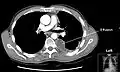

A pleural effusion appears as an area of whiteness on a standard posteroanterior chest X-ray.[15] Normally, the space between the visceral pleura and the parietal pleura cannot be seen. A pleural effusion infiltrates the space between these layers. Because the pleural effusion has a density similar to water, it can be seen on radiographs. Since the effusion has greater density than the rest of the lung, it gravitates towards the lower portions of the pleural cavity. The pleural effusion behaves according to basic fluid dynamics, conforming to the shape of pleural space, which is determined by the lung and chest wall. If the pleural space contains both air and fluid, then an air-fluid level that is horizontal will be present, instead of conforming to the lung space.[16] Chest radiographs in the lateral decubitus position (with the patient lying on the side of the pleural effusion) are more sensitive and can detect as little as 50 mL of fluid. Between 250 and 600mL of fluid must be present before upright chest X-rays can detect a pleural effusion (e.g., blunted costophrenic angles).[17]

Chest computed tomography is more accurate for diagnosis and may be obtained to better characterize the presence, size, and characteristics of a pleural effusion. Lung ultrasound, nearly as accurate as CT and more accurate than chest X-ray, is increasingly being used at the point of care to diagnose pleural effusions, with the advantage that it is a safe, dynamic, and repeatable imaging modality.[18] To increase diagnostic accuracy of detection of pleural effusion sonographically, markers such as boomerang and VIP signs can be utilized.[19]